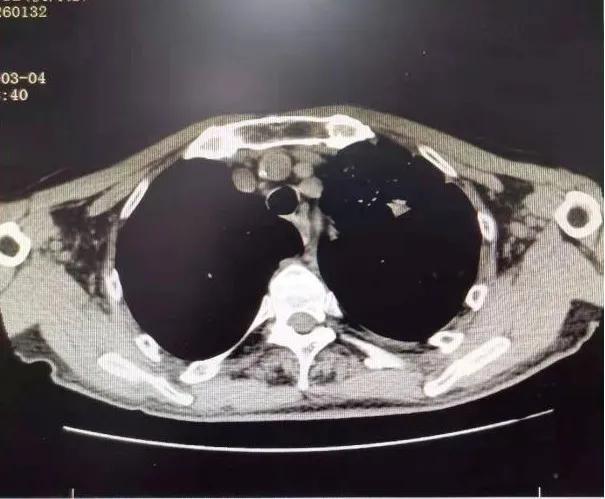

75岁的张爷爷患有慢性阻塞性肺疾病、脑栓塞等多种慢性病,体质较差,PS评分为3分,入院时有咳嗽咯血伴有气短乏力等症状,查胸部CT可见左上肺叶大小约8×4cm大小占位病变,纵隔淋巴结肿大,左侧大量胸腔积液。 气管镜可见左上支气管内新生物阻塞。 病理提示: 鳞状细胞癌。 诊断为: 肺癌(左肺 鳞癌 cT4N2M1a,IVA期)。 确诊后家属考虑患者年老体弱,合并多种疾病,拒绝放化疗,准备放弃治疗。

1个月后张爷爷来院复诊,复查胸部CT提示:左肺上叶肿块缩小到1cm,肺不张明显缓解,胸腔积液减少 。 张爷爷表示近1月来状态明显好转,未再咯血,活动也不像之前那样一动就喘,平时走路吃饭都不影响。入院后PS评分1分,临床疗效评估为PR。 为更好的控制肿瘤,进行了第二次介入治疗。 行支气管动脉及胸廓内动脉造影后显示肿瘤染色明显减少,继续灌注化疗药物后,将肿瘤滋养动脉进行了彻底栓塞。 术后无不适, 顺利完成第二次治疗。